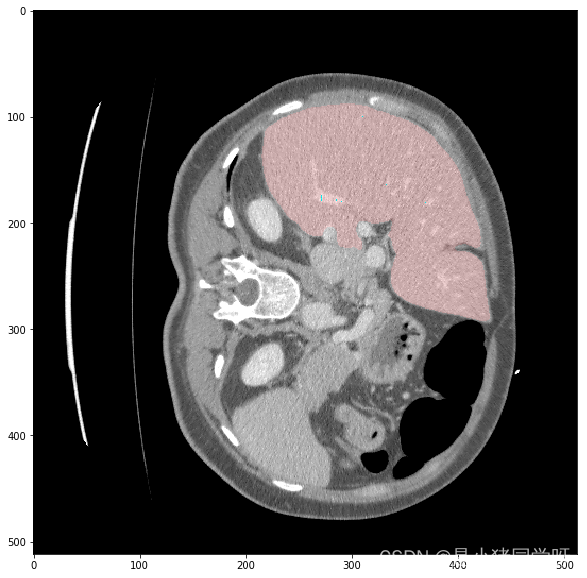

经过测试,肝脏和肝脏肿瘤分割系统的各项功能都能够正常工作,满足用户需求。在白盒测试方面,覆盖了网络结构、特征提取、特征映射、损失函数等方面,没有发现明显的问题。在黑盒测试方面,采用了等价类划分、边界值分析、因果图和错误推测等方法,测试结果表明系统的各项指标均符合要求,没有发现明显的问题。

本次测试结果表明,肝脏和肝脏肿瘤分割系统的各项功能都能够正常工作,满足用户需求。在白盒测试和黑盒测试方面,测试覆盖了网络结构、特征提取、特征映射、损失函数、上传CT影像、查看分割结果、后处理、性能评估、恢复测试、安全测试、强度测试和性能测试等方面,测试结果表明系统的各项指标均符合要求,没有发现明显的问题。